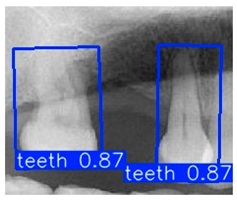

Although YOLOv10n-OBB demonstrated a slight advantage in overall classification accuracy, YOLOv8n-OBB achieved a relatively higher mAP50–95 of 78.75%. Furthermore, as illustrated in Figure 12, YOLOv8n-OBB generated predictions with higher confidence scores, and its detection boxes more comprehensively encompassed critical surrounding structures of the teeth, including both the crown and root regions. In contrast, YOLOv10n-OBB, despite exhibiting better classification accuracy, often produced detection boxes with insufficient coverage or positional deviations, which could compromise the accuracy and stability of subsequent localization and contour segmentation tasks. Considering both model performance and practical image application, the stable and reliable predictions provided by YOLOv8n-OBB better meet the requirements of fine-grained dental feature recognition. Moreover, its robustness is advantageous for downstream applications such as auxiliary line generation and implant pathway orientation.

Figure 12.

YOLO-OBB segmentation comparison.